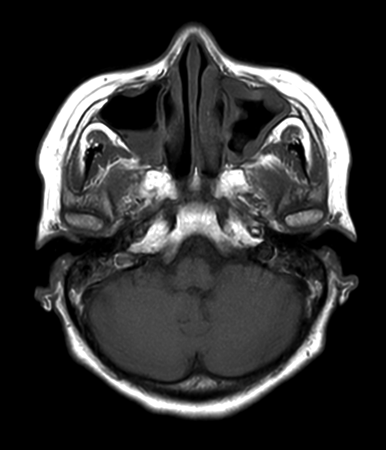

Axial mDIXON XD - T2w TSE (In Phase)